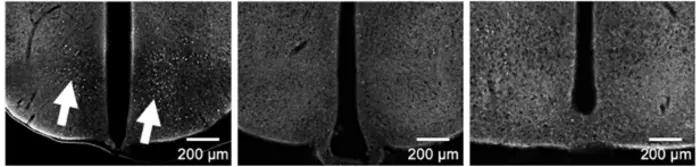

The results showed that the experimental group treated with the electronic therapy exhibited statistically significant nerve regeneration compared to the control group. The therapy also successfully targeted specific brain areas, with no damage to surrounding cells or other regions of the brain, demonstrating its safety and innovation compared to existing non-invasive methods.

This innovative micro-shockwave electronic therapy opens new horizons in non-invasive brain disorder treatment by significantly reducing the risks associated with traditional surgical methods. It not only overcomes the limitations of existing non-invasive methods by allowing targeted stimulation of specific brain areas but also induces various brain cell signals, such as cell differentiation and proliferation, without harming brain function (see Fig. 4). This breakthrough is seen as a major advancement in the treatment of brain disorders.